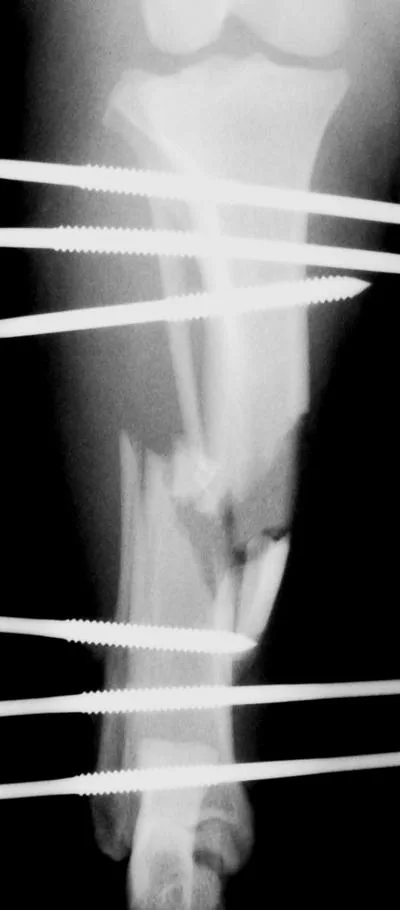

External Fixators

External fixators are often used for biologic management of fractures because of the lower implant cost and relative ease of application. External fixators can be used with closed or open reduction of the fracture. When applied correctly, vascular supply of the fracture fragments can be effectively preserved. Linear external fixators (Figures 3A, B) are most commonly used, but circular fixators are gaining popularity and have advantages for some fracture types. This tibia and fibula fracture achieved bony union in 7 weeks.